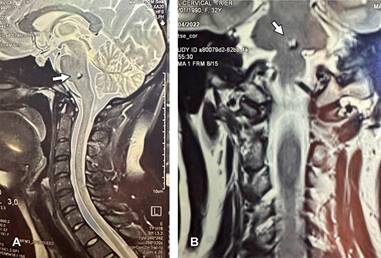

Imágenes de resonancia magnética ponderadas en T2, en corte sagital (A) y coronal (B) de columna cervical y parte del cráneo en paciente femenino de 37 años asintomática neurológicamente. Se observa, como hallazgo incidental, lesión de 3 mm en zona inferior central de la protuberancia.

Figura 1: